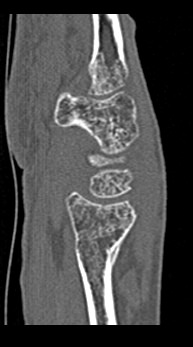

Лучезапястный сустав имеет сложное строение. Это комбинированное сочленение между костями предплечья и кистью руки. Сустав имеет множество анатомических структур, включая мелкие кости запястья (трехгранную, полулунную, ладьевидную, гороховидную, кость-трапецию, трапециевидную, головчатую и крючковидную), а также внутрисуставные диски, связки, мышцы и сухожилия, обеспечивающие гибкость и высокую подвижность сустава.

Метод КТ основан на использовании ионизирующего излучения и способности тканей поглощать рентгеновские лучи. Костные ткани обладают высокой плотностью и способны активно поглощать рентгеновские лучи, поэтому они хорошо видны на снимках КТ. В отличие от обычного рентгена компьютерный томограф послойно сканирует исследуемую область в нескольких плоскостях, благодаря чему получаются снимки в мельчайших подробностях. Затем с помощью цифровой обработки данных, полученных при КТ-сканировании, создаются объемные модели области исследования.

Таким образом, мультиспиральная компьютерная томография позволяет оценить состояние всех структур лучезапястного сустава, выявить травматические повреждения, признаки воспалительных заболеваний, диагностировать аномалии развития и опухолевые образования. При травмах на снимках и трехмерных изображениях хорошо видны фрагменты костных отломков, эти данные используются при подготовке к оперативным вмешательствам. После операции результаты КТ позволяют оценить правильность репозиции костных структур, выявить послеоперационные осложнения, отследить в динамике процесс восстановления тканей.